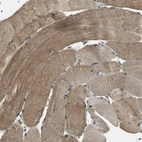

Immunohistochemical staining of human skeletal muscle shows moderate cytoplasmic positivity in myocytes.